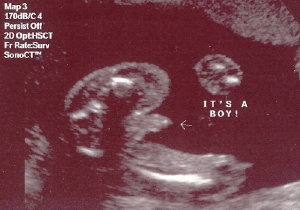

My Latest Ultrasound.... I just had an ultrasound on Tuesday, July 11th. I was so excited that all ate that morning was a Chewy Granola Bar. The ultrasound was at 1:00 p.m., so during the ultrasound, I almost fainted. The room started to go black. My body temperature felt like it was dropping, BUT I broke out in a sweat, and the sound drained from the room. All I could do was grab Duane's hand, as if holding on for my dear life. Go figure. Can anybody say "low blood sugar." Oh well. My husband gave me the whole lecture on how breakfast is the most important meal of the day, etc.... So you can all save your preaching for another day, thank you very much. Other than that, the whole day was so exciting! WE'RE HAVING A BOY! Here are some ultrasound pictures for you. Sorry they're not that clear but it's better than nothing, right? Enjoy...